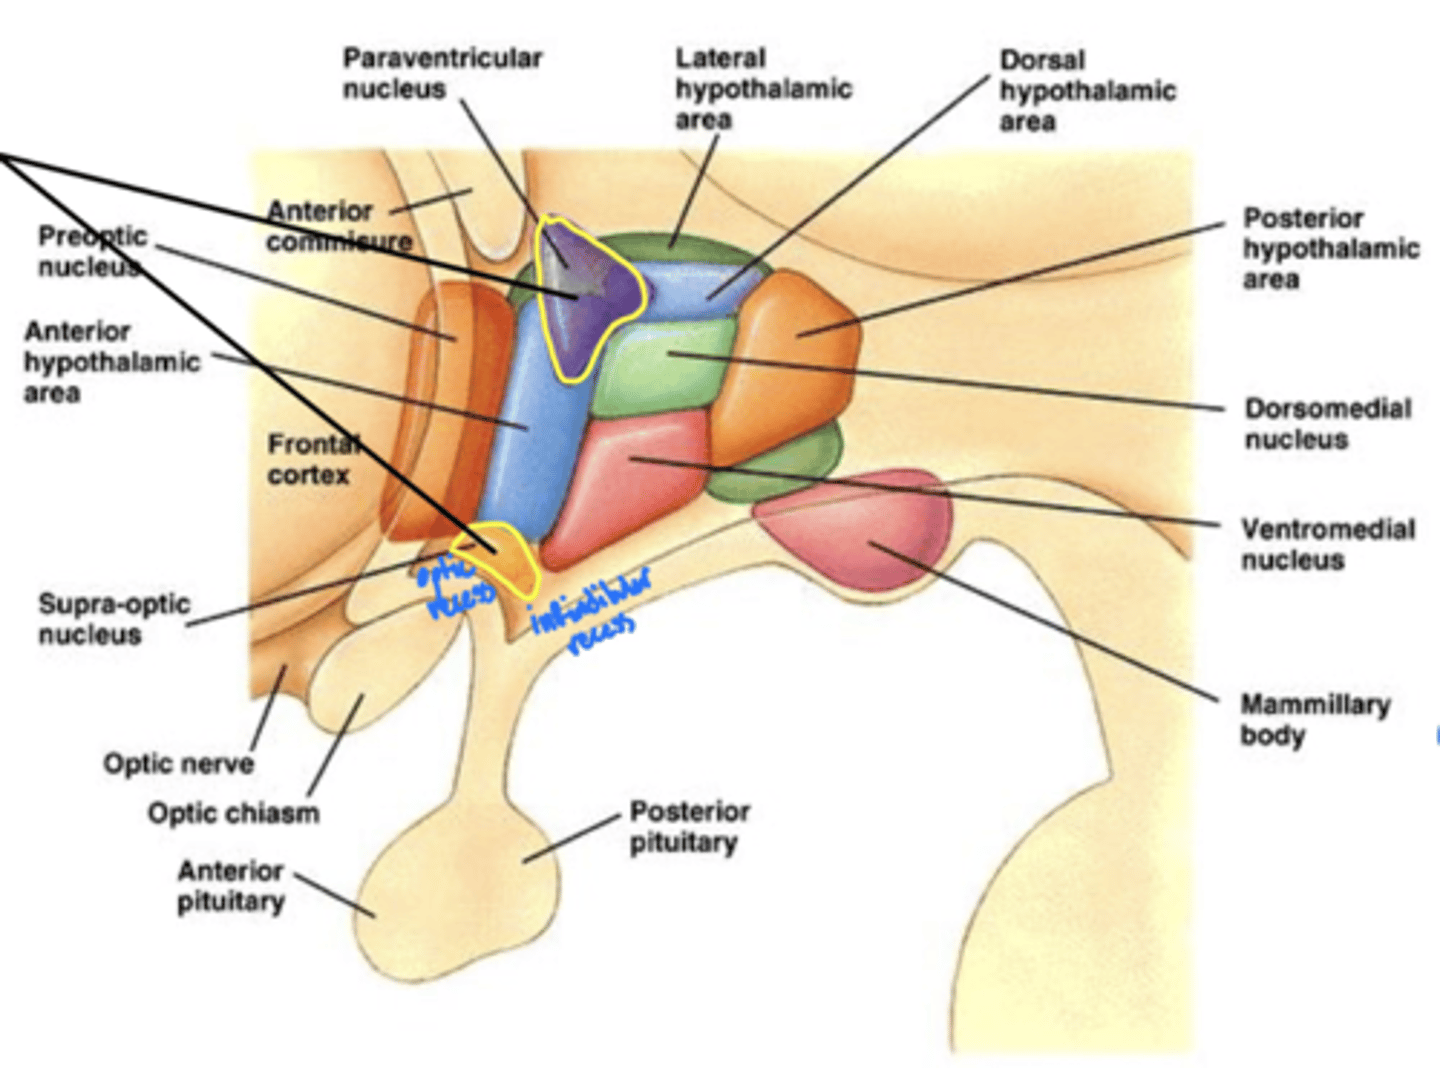

What is the function of the hypothalamus?

homeostasis

What is the hypothalamus just superior to?

1. optic chiasm

2. pituitary gland

What nuclei of the hypothalamus produce hormones for the pituitary gland?

1. paraventricular nucleus

2. supra-optic nucleus

Where is the hypothalamus in relation to the thalamus?

anteroinferior (in front and below)